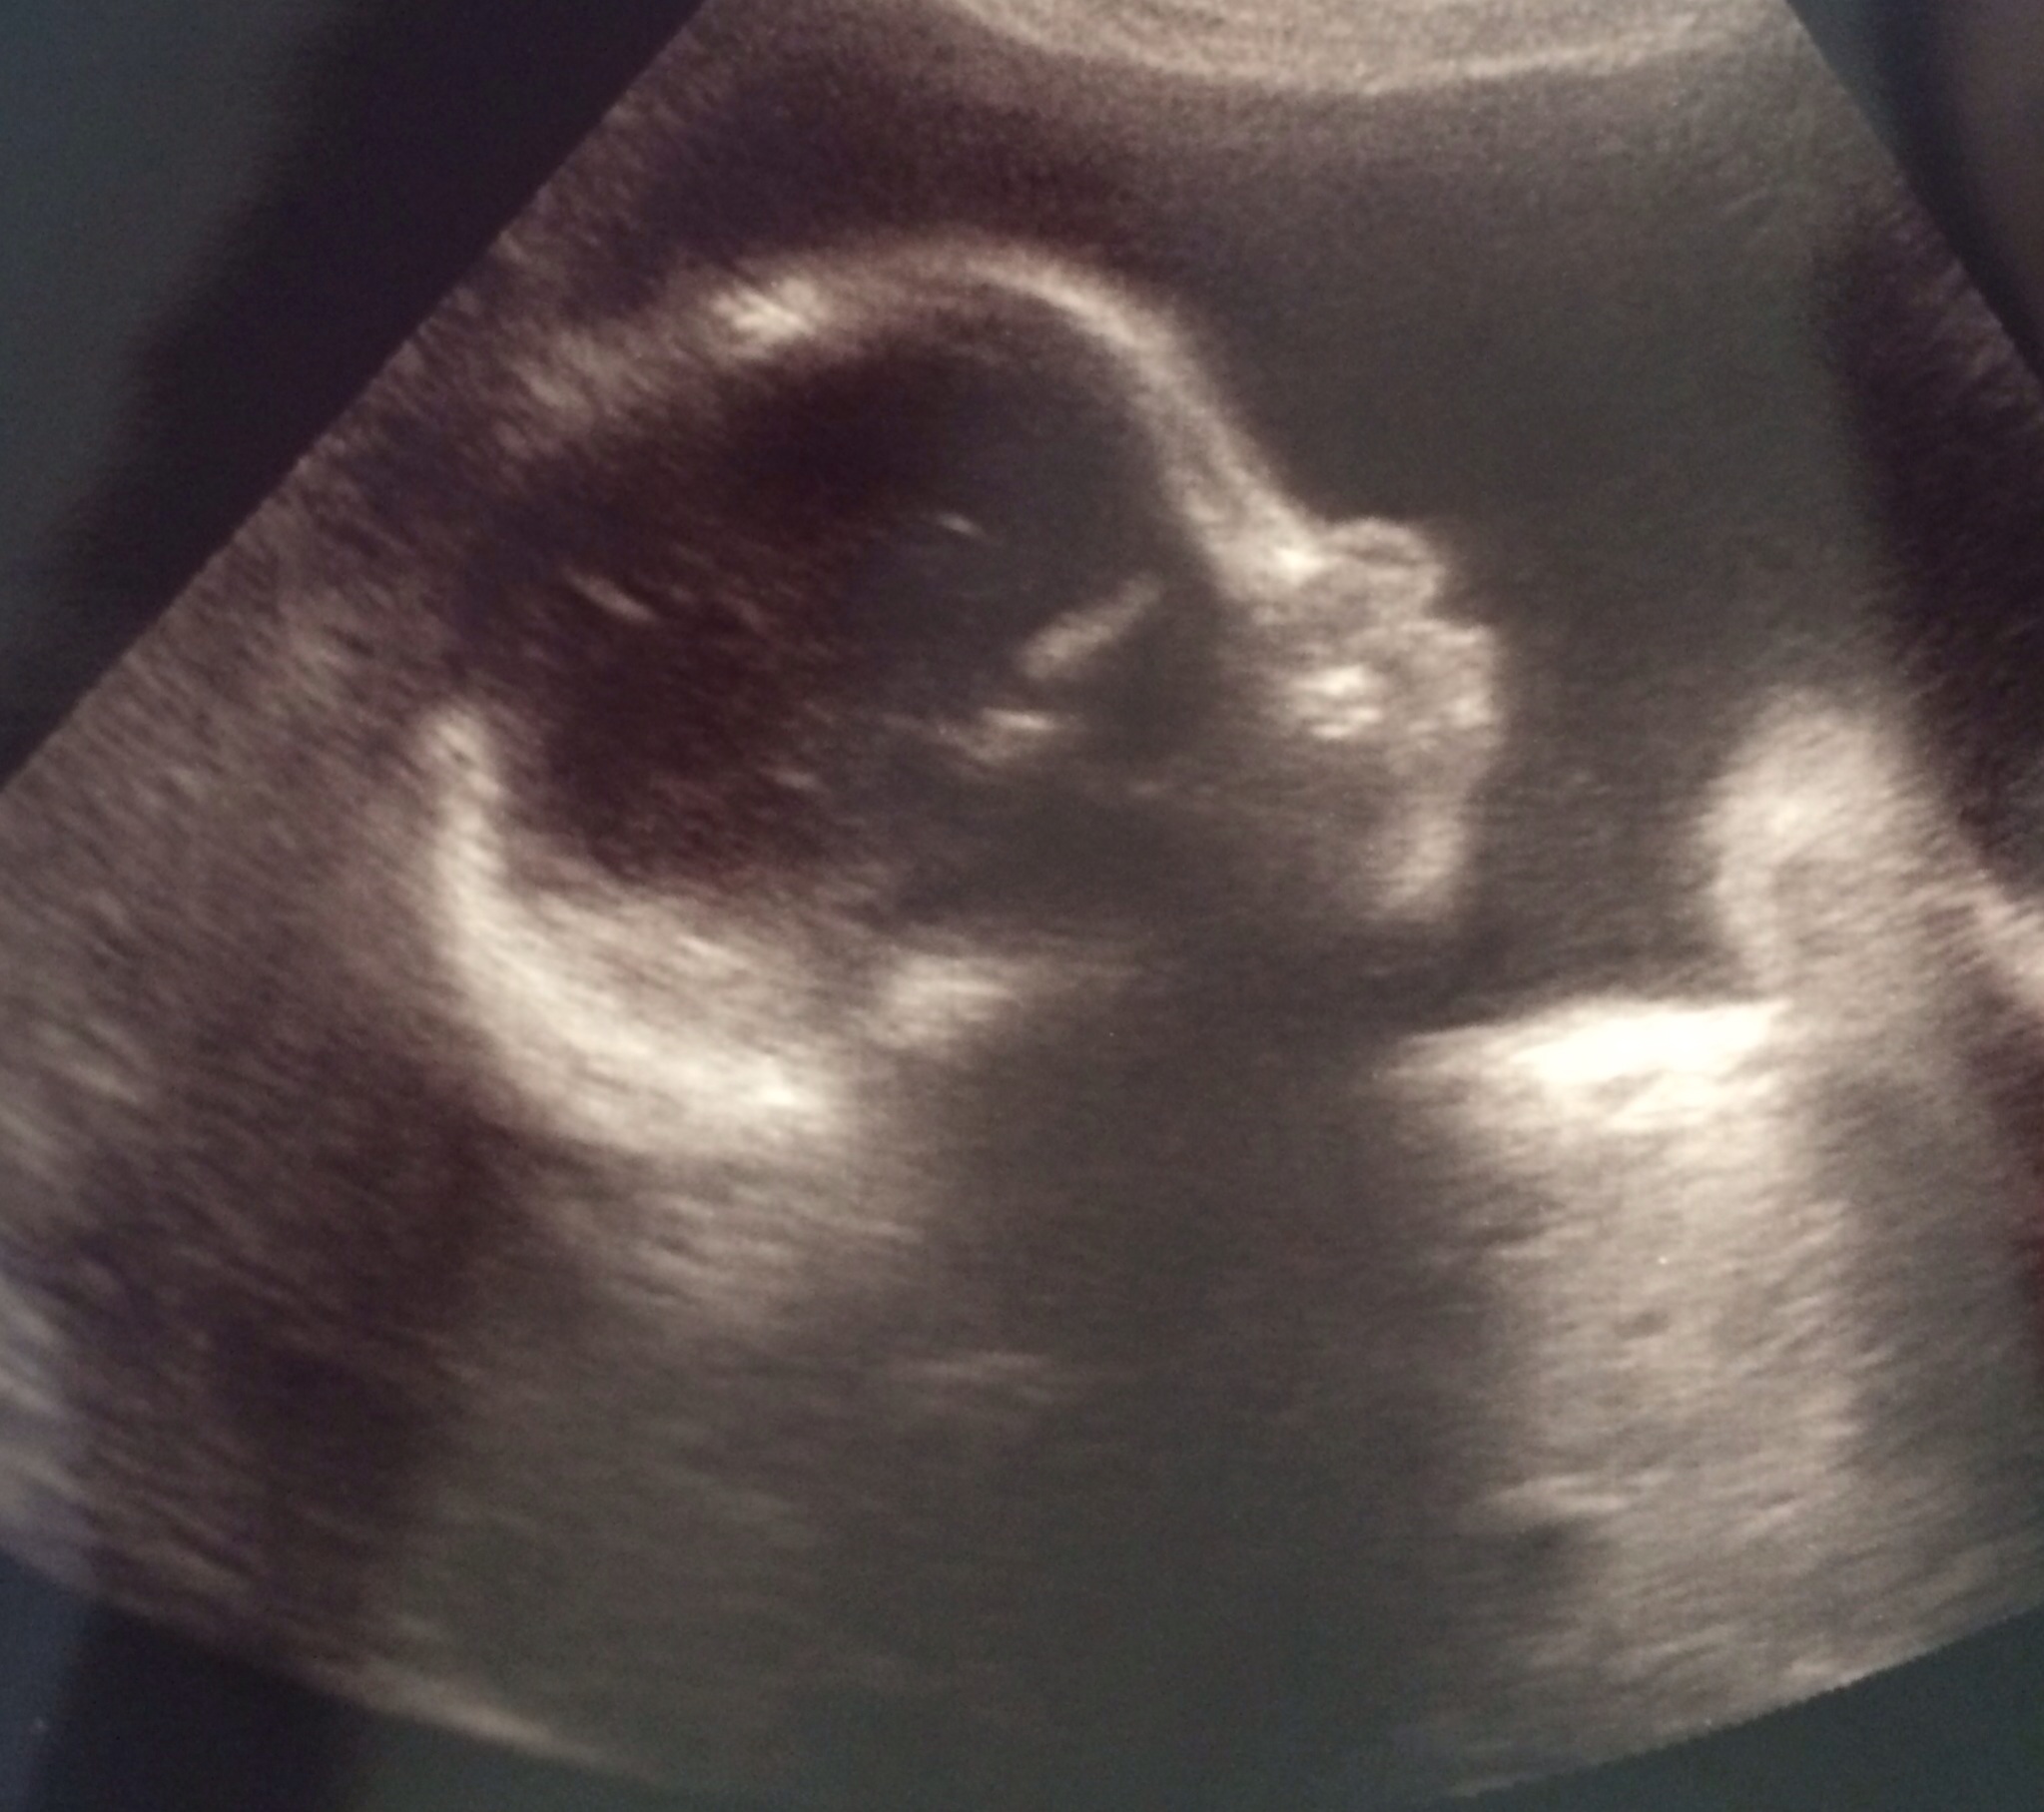

I also got to see our little princess (yes, I call her a princess) today and she is growing and measuring perfectly at 2lbs 7oz.  BUT she is breach right now (I had a feeling she might be based on where I feel her kicks).  NP said she still has time to flip so I'm not too concerned. And even if she doesn't flip and I have to have a c-section then that's totally fine.

So that is all - just wanted to AW my awesome experience with a new doctor since I've been having such a shitty time with my old practice. Oh and here is my little Valentine for your viewing pleasure :)